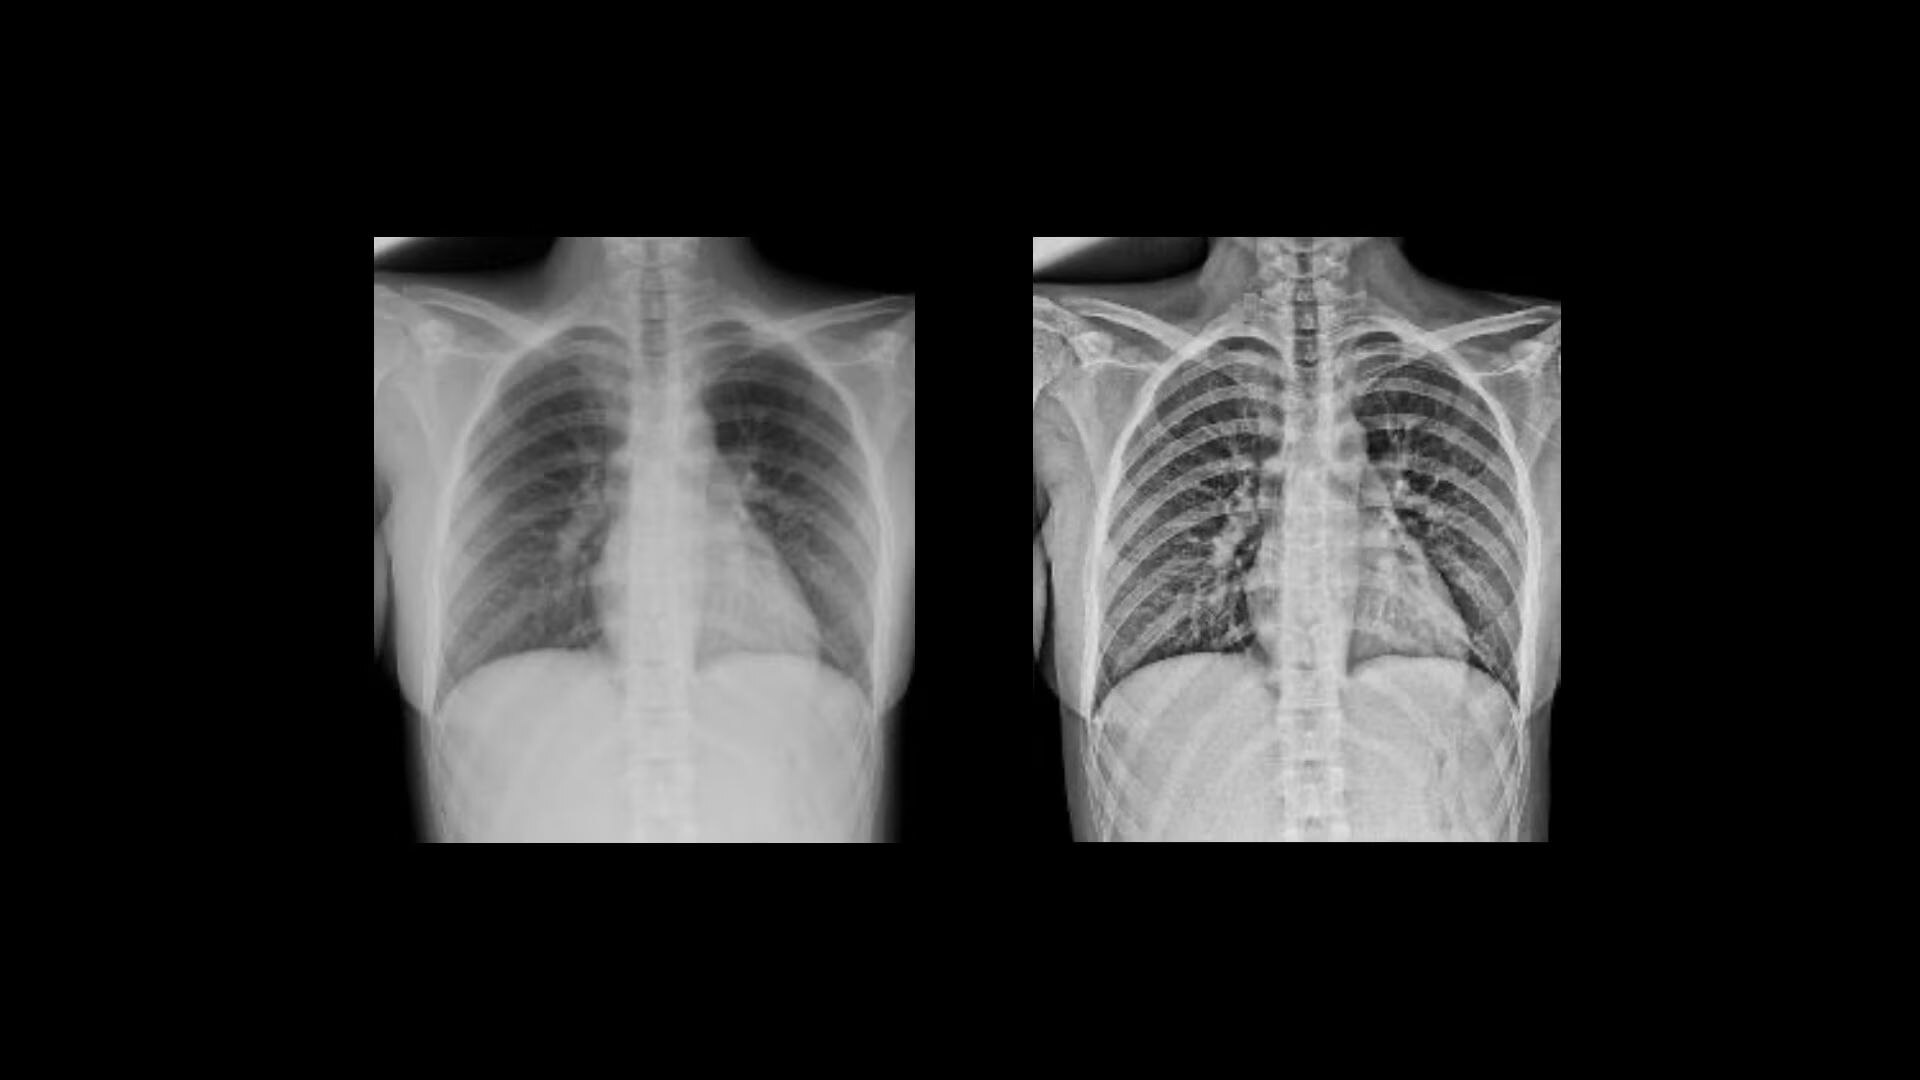

Harness AI for improved consistency

Automated AI Brightness and Contrast (AIBC)

delivers consistent brightness and contrast for 56* anatomy and view combinations regardless of variations in dose, patient positioning, field of view and metal implants. By automatically adjusting brightness and contrast to a user-defined preference, Helix's AIBC can help reduce technologist image processing time by up to 87%.¹